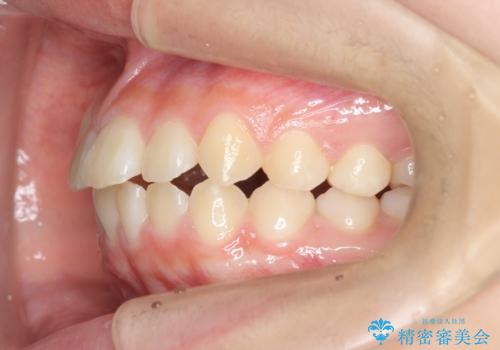

インビザラインで行う八重歯の治療

- 笑った時に目立つ八重歯の矯正治療を求めて来院されました。

マイクロインプラントを用いた臼歯の後方牽引、およびゴムかけ等の付加処置を駆使して八重歯の治療を行っていきます。

しっかりとゴムかけを頑張っていただいたおかげで、上顎臼歯の後方移動が達成されしっかりとした噛み合わせの構築と、八重歯の治療を達成することができました。